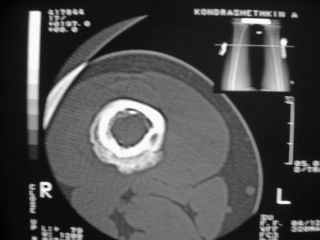

Здравствуйте, уважаемые коллеги!Представляю вашему вниманию интересный случай и пока что непонятный для меня в диагностическом плане. На днях в наше отделение (детской ортопедии и травматологии) поступил 13-летний мальчик по направлению из поликлиники с диагнозом: остеома нижней трети правого бедра.

Анамнез практически никакой: в следствие травмы (растяжение связок коленного сустава) от 07.11.2004 выполнены Rg-граммы в травмпункте и обнаружено опухолевидное образование. Первичные Rg-граммы я не публикую, так как они заметно худшего качества, да и динамики за прошедшие три недели не отражают. Болевой синдром купирован в течение трёх дней. В настоящий момент мальчика ничего не беспокоит. Ходьба не нарушена, опухоль пальпируется с трудом по задней поверхности в н\3 правого бедра, пальпация безболезненна, объем движений в суставах правой нижней конечности полный и симметричный. Кожа над опухолью не изменена.В нашей клинике проведено дополнительное обследование: общие анализы крови и мочи, биохимия крови без особенностей. Выполнены Rg-граммы на цифровом Siemens обычные и продольные томограммы срезами 3-5 мм, а также компьютерная томография поперечными срезами по 5 мм. Прошу обратить внимание, что на приведённых томограммах видны две полости 10х15 мм и 15х60 мм. Также имеются два опухолевидных образований наслаивающихся друг на друга: уплощённое и вытянутое 10х100 мм и элипсовидной формы 15х30 мм. Это хорошо заметно на фото a_1.jpg c_1.jpg и d_1.jpg. Плотность внутри полостей 125% от плотности костномозгового канала, плотность наружного опухолевидного образования 55% от плотности кортикального слоя. Также отмечается линия перелома по центру наружного опухолевидного образования.Исходя из полученных данных мнения в плане диагноза несколько разделились от 1)сочетания кортикальной фиброзной дисплазии и латентно протекавшего маршевого перелома н\3 правого бедра до 2)остеосаркомы. В отношении первого варианта не сходится отсутствие клиники при переломе такой крупной кости как бедро, второй вариант вообще оставлю без комментария, ибо некомпетентен. Хотелось бы услышать мнения коллег, с удовольствием ознакомлюсь с любыми предположениями и замечаниями.С уважением, Александр Е. КлоковОтделение детской ортопедии и травматологииБСМП г. Мурманска.